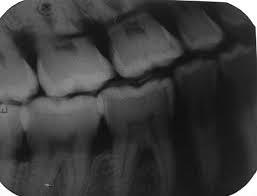

ERRORES RADIOGRÁFICOS OBSERVE LAS SIGUIENTES IMÁGENES. ELLAS LE MOSTRARÁN EL ERROR EN CADA UNA DE LAS SIGUIENTES RADIOGRAFÍAS .

Radiografía Sobre expuesta Los interproximales no se pueden apreciar ya que el cono de la máquina no dirigió los rayos centralizados y cada pieza dental cubre a la adyacente.